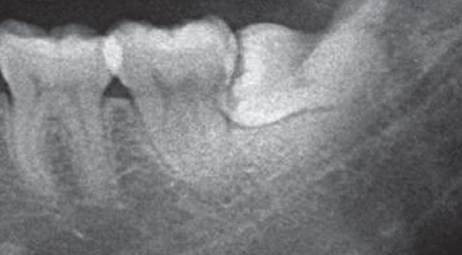

智齒根部阻力分析及操作圖解

下面將為您介紹智齒根部阻力分析及操作圖解的相關內容,這將會花費您約兩到三分鐘的時間進行瀏覽,感謝您的閱讀: